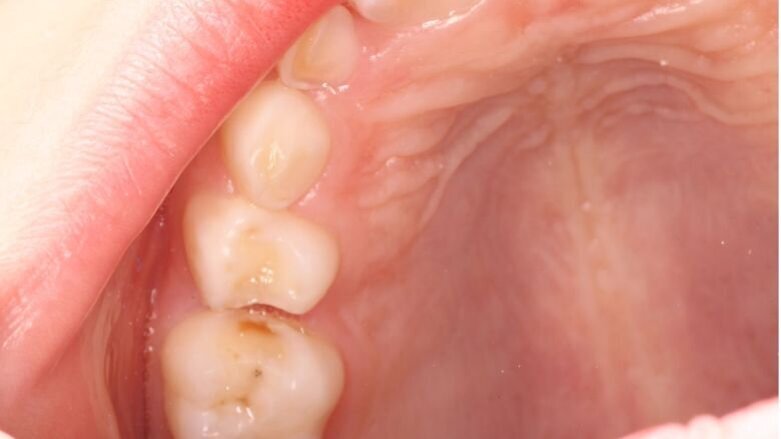

Er wordt bij periodiek mondonderzoek weinig plaque aangetroffen. Sommige laesies zijn inactief en andere worden of blijven actief (afbeelding 3a-c). De 75 werd na een half jaar van een Atraumatic Restorative Treatment (ART)-restauratie voorzien wegens gevoeligheid. Na 2 jaar trad ’s nachts pijn op aan de 64, maar deze verdween weer. Achteraf was het beter geweest als de 64 ook met ART was gerestaureerd (afbeelding 4a-b). Moeder is tevreden over de behandeling na 4 jaar, maar wij zullen nog beter ons best doen om meer zicht te krijgen op de mondverzorging thuis en daar de behandeling op afstemmen. Hoe dan ook, een narcosebehandeling is deze jonge patiënte gelukkig bespaard gebleven.

Afbeelding 3a. Cariëslaesies onderkaak rechts.

Afbeelding 3b. Cariëslaesies ruim half jaar later stabiel.

Afbeelding 3c. Cariëslaesie 64 na een half jaar nog actief.